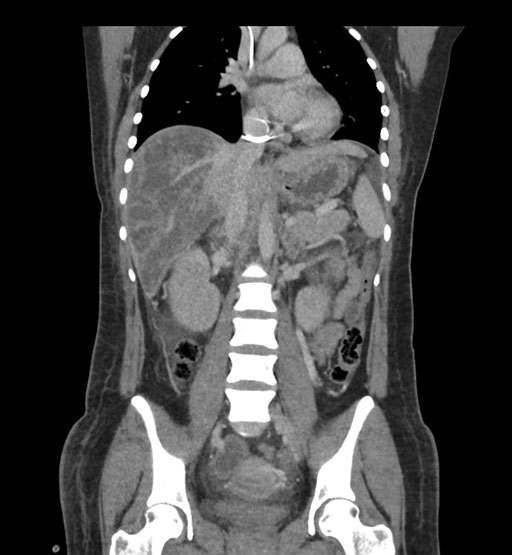

Coronal Arterial

Imaging analysis

Based on initial findings, which issue(s) would you be most concerned about?